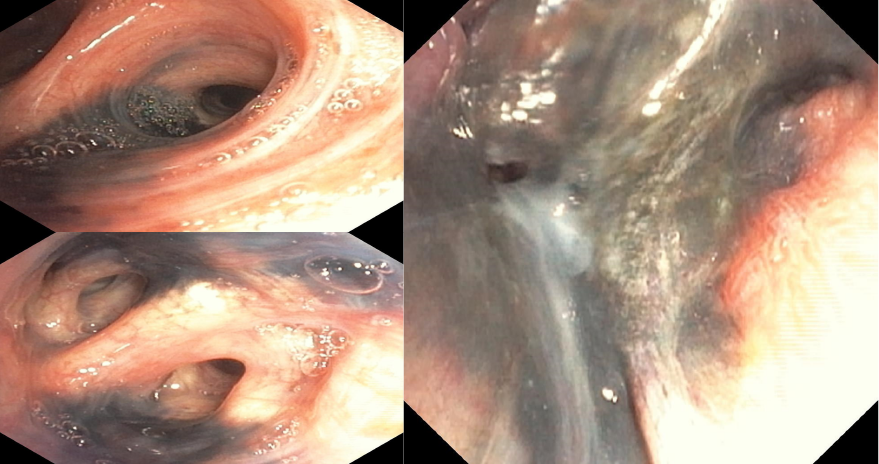

Figura 1.

Fotos tomadas de broncoscopias. Imagen A: Mucosa de segmentos bronquiales con manchas antracóticas. Imagen B: Mucosa de segmentos bronquiales con manchas antracóticas y distorsión. Imagen C: Mucosa de segmentos bronquiales con manchas antracóticas, distorsión y estenosis (antracoestenosis).